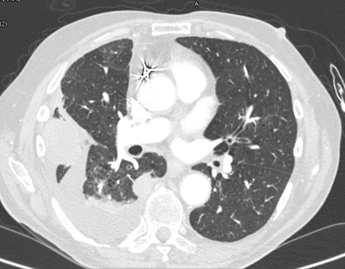

A CT scan was thereafter performed which

demonstrated multiple pleural-based nodules and masses,

the largest of which was adjacent to right 6th and 7th ribs and measured 3.3cm x 4.7cm (figure 2)

Figure 2. CT scan: multiple pleural-based nodules and masses,

the largest of which was adjacent to the right 6th and 7th ribs.